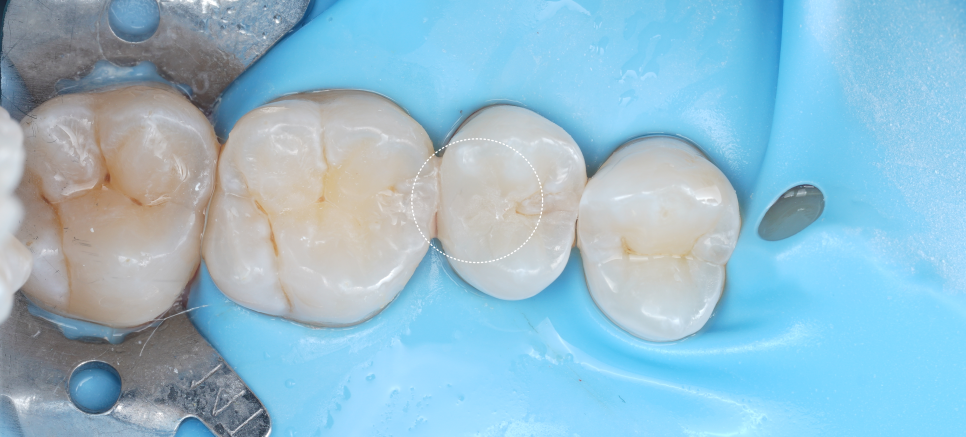

이때, 러버댐으로 침과 습기를 완전히 차단해 재료가 제대로 붙을 수 있는 환경을 만들어줬어요. 그다음 신경 노출 부위에 MTA를 도포하여 신경을 안정시켰어요.

촬영일 : 251013

마지막으로 레진을 여러 겹 쌓아 올리며 형태를 복원했는데요. 씹는 힘의 방향, 인접 치아와의 접촉점, 미세한 높낮이까지 모두 고려하면서 자연스러운 형태로 완성했어요.

촬영일 : 251013 / 251013